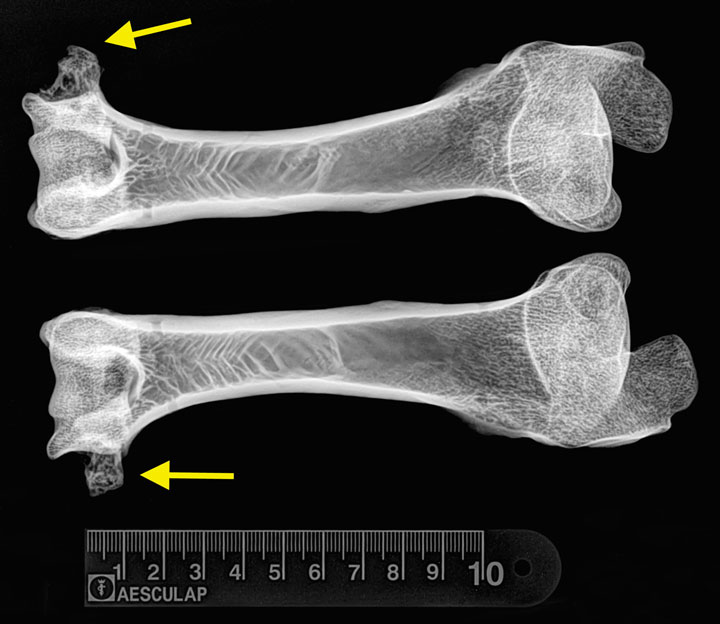

READY FOR A CLOSE-UP Dolly the Sheep’s bones were X-rayed to determine whether the sheep was plagued by arthritis linked to cloning.

University of Nottingham